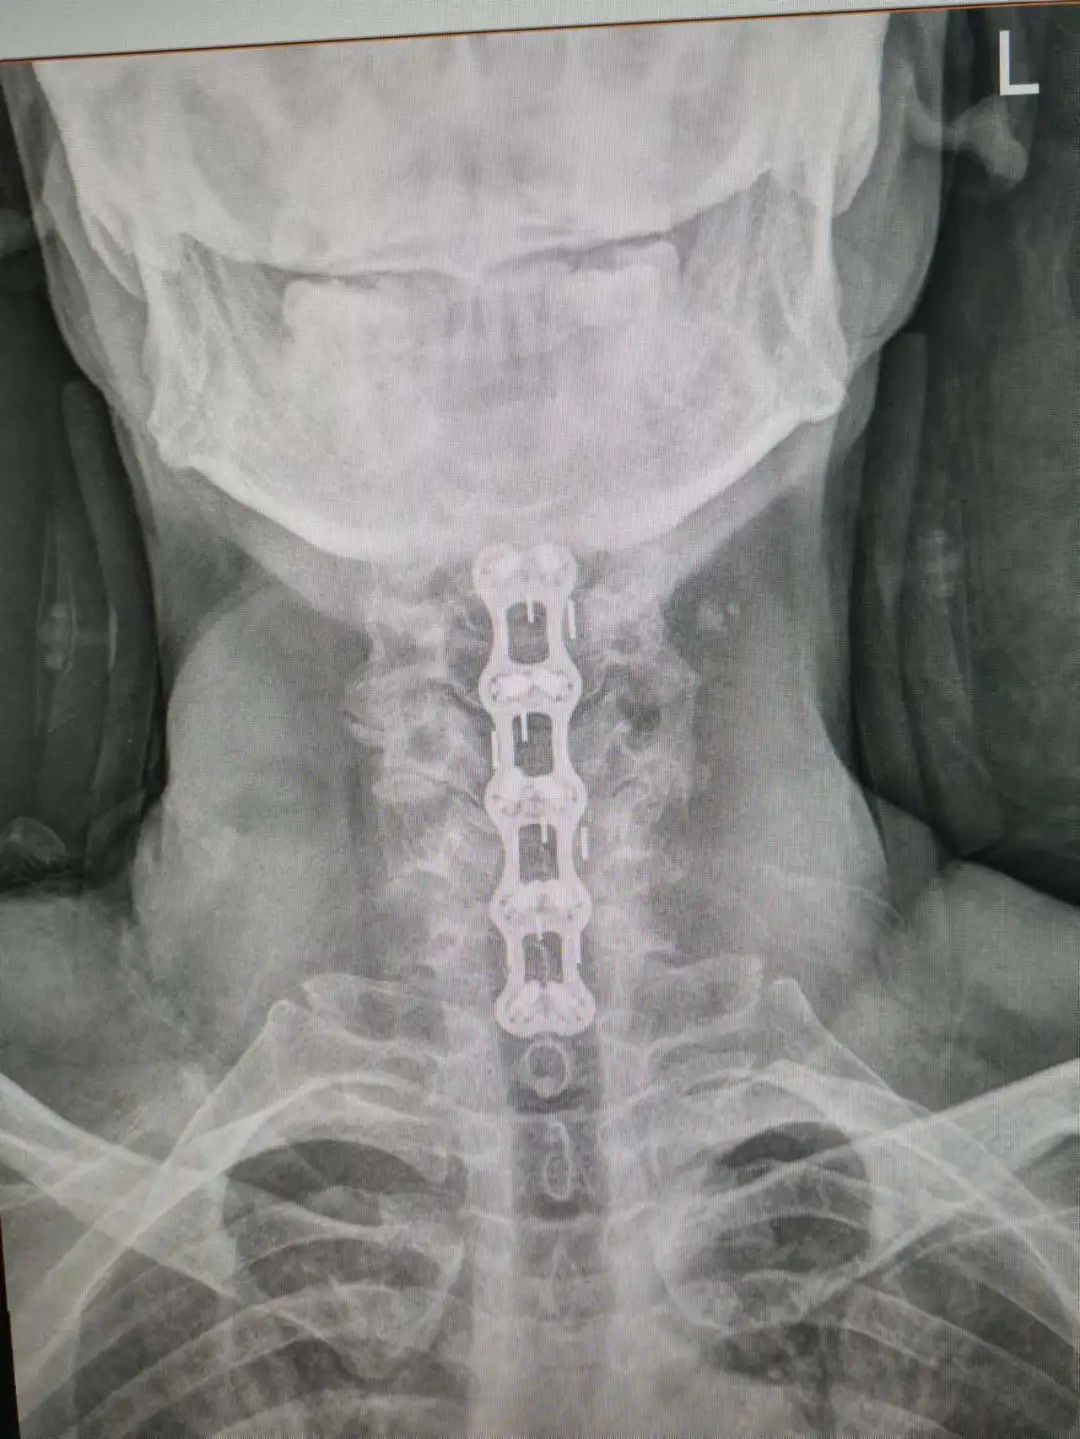

楊先生脊髓性頸椎病拍片

由于楊先生的病情嚴(yán)重,需住院治療。楊先生入院后,瀘州市中醫(yī)醫(yī)院骨傷二科科主任楊陳一制定了手術(shù)計(jì)劃,決定脊髓型頸椎病的手術(shù)從前路切開減壓,頸3/4 、頸4/5、 頸5/6、 頸6/7椎間盤切除,椎間融合,鋼板內(nèi)固定術(shù)手術(shù),而腰椎管狹窄癥經(jīng)后路切開減壓,腰3/4、腰4/5椎同盤動(dòng)除,椎間融合、釘棒系統(tǒng)內(nèi)固定術(shù)。

楊先生術(shù)后拍片